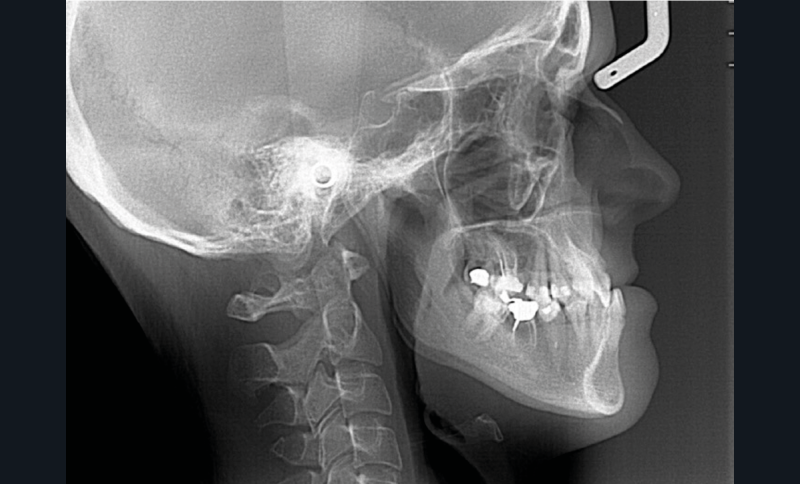

Diagnostic (fig. 1a-g)

La patiente présente une classe III squelettique dans un contexte hyperdivergent associée à une endoalvéolie maxillaire, un articulé inversé antérieur, une rétroversion incisive maxillaire, des rapports de classe I canine bilatérale, une absence de 16 et 36.

Au niveau esthétique, le profil est rectiligne. La lèvre supérieure est plus effacée, en retrait par rapport à la lèvre inférieure. De face et de profil, la mandibule paraît massive et le maxillaire effacé : le manque de soutien de la lèvre supérieure contribue à cette impression.

Le sourire est étroit, dégradé par les malpositions dentaires.

Au niveau fonctionnel, il existe un pro-glissement mandibulaire et un articulé inversé antérieur. Le profil téléradiographique montre en occlusion des rapports labiaux et un profil de classe III plus marqué que sur photographies.